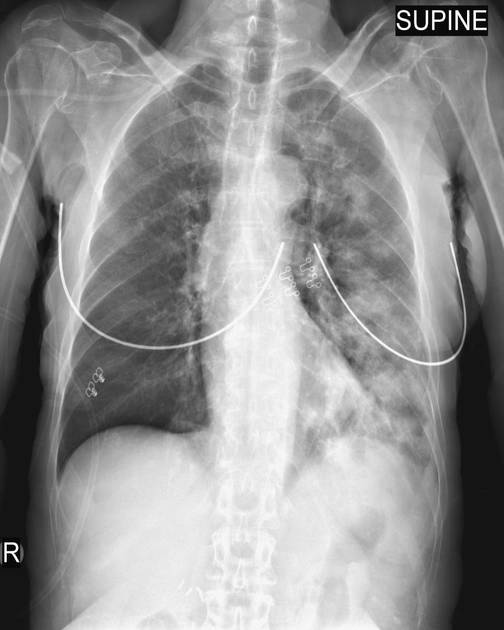

CXR shows:

🦠 Patchy, basilar, nodular, & round opacities (often +effusion)

🦠 Necrotizing PNA & Pseudo-necrosis (spillage into pre-existing cavity)

🦠 Abscess & Empyema (+hydropneumothorax if empyema)